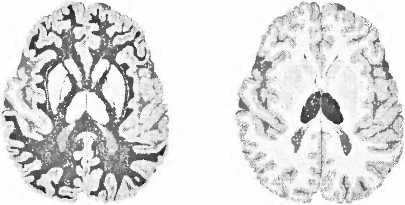

Мы осознаём наше окружение и себя самих. Некоторые структуры мозга имеют решающее значение для этого осознания: кора больших полушарий, таламус, куда стекается информация от наших органов чувств, и белое вещество — нервные волокна между структурами (рис. 19). После инсульта в правом полушарии может быть частично затронуто как самосознание, так и осознание окружающего пространства. В некоторых случаях больной не осознает свое левостороннее поражение и игнорирует как в окружающем пространстве, так и в своем собственном теле всё, что находится слева. Это состояние обозначают как неглект (игнорирование). Если вы подойдете слева к кровати больного, он вас не воспринимает, хотя может поворачивать голову и может вас видеть. Читая газету, больной видит только правую сторону. Рисуя часы, кошку или цветок, он изображает только их правую часть. С тарелки он съедает только то, что лежит в ее правой половине; если же повернуть тарелку на 180°, он съедает и вторую половину порции. Игнорирование может затронуть и левую часть собственного тела. Тогда свою левую руку или левую ногу он не воспринимает как свои собственные. Больной не одевает и не моет свою левую сторону и причесывает волосы только справа.

Рис. 19. Для сознания важны три здоровые и хорошо функционирующие структуры мозга, здесь они помечены черным. Слева — здоровая кора больших полушарий. Справа — таламус. Посредине — белое вещество, где осуществляется связь между корой и таламусом.